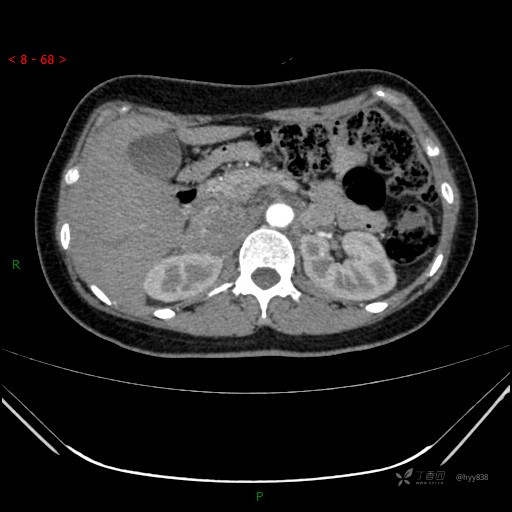

辅助检查:CT

临床诊断:肾上腺占位